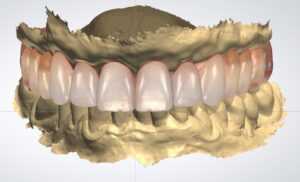

Successivamente inizierà la fase di progettazione, dove un programma dedicato elaborerà tutti i dati acquisiti. Inoltre verra’ coinvolto il Tecnico, che svilupperà il progetto Protesico definitivo, da sottoporre ad approvazione del paziente prima dell’intervento

Dopo aver stabilito la nuova estetica del paziente, verranno progettati gli impianti e successivamente la dima chirurgica.